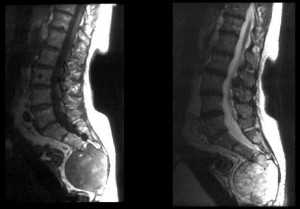

Изменения на МРТ по типу MCh1 характеризуются гипоинтенсивным сигналом на T1-взвешенных изображениях (ВИ), гиперинтенсивным — на Т2-ВИ и изображениях, полученных в Т2 с жироподавлением (T2-FS) или STIR режимах (рис. 1). Интенсивность сигнала увеличивается после введения гадолиния, эти МРТ-признаки соответствуют отеку костного мозга. Результаты микро-компьютерной томографии (микро-КТ) [11] и гистопатологического анализа [2, 12] демонстрируют разрушение и растрескивание КПП, ассоциированное с утолщением костных трабекул и увеличением числа остеобластов и остеокластов, поддерживающих повышенную активность ремоделирования кости. Также выявляется замена нормальной ткани костного мозга на богато васкуляризированную грануляционную ткань.

Рис. 1.ИзменениянаМРТпотипу MCh1. 1 — гипоинтенсивный сигнал на T1-ВИ; 2 — гиперинтенсивный сигнал на Т2-ВИ; 3 — гиперинтенсивный сигнал в режиме с подавлением сигнала от жира (STIR).